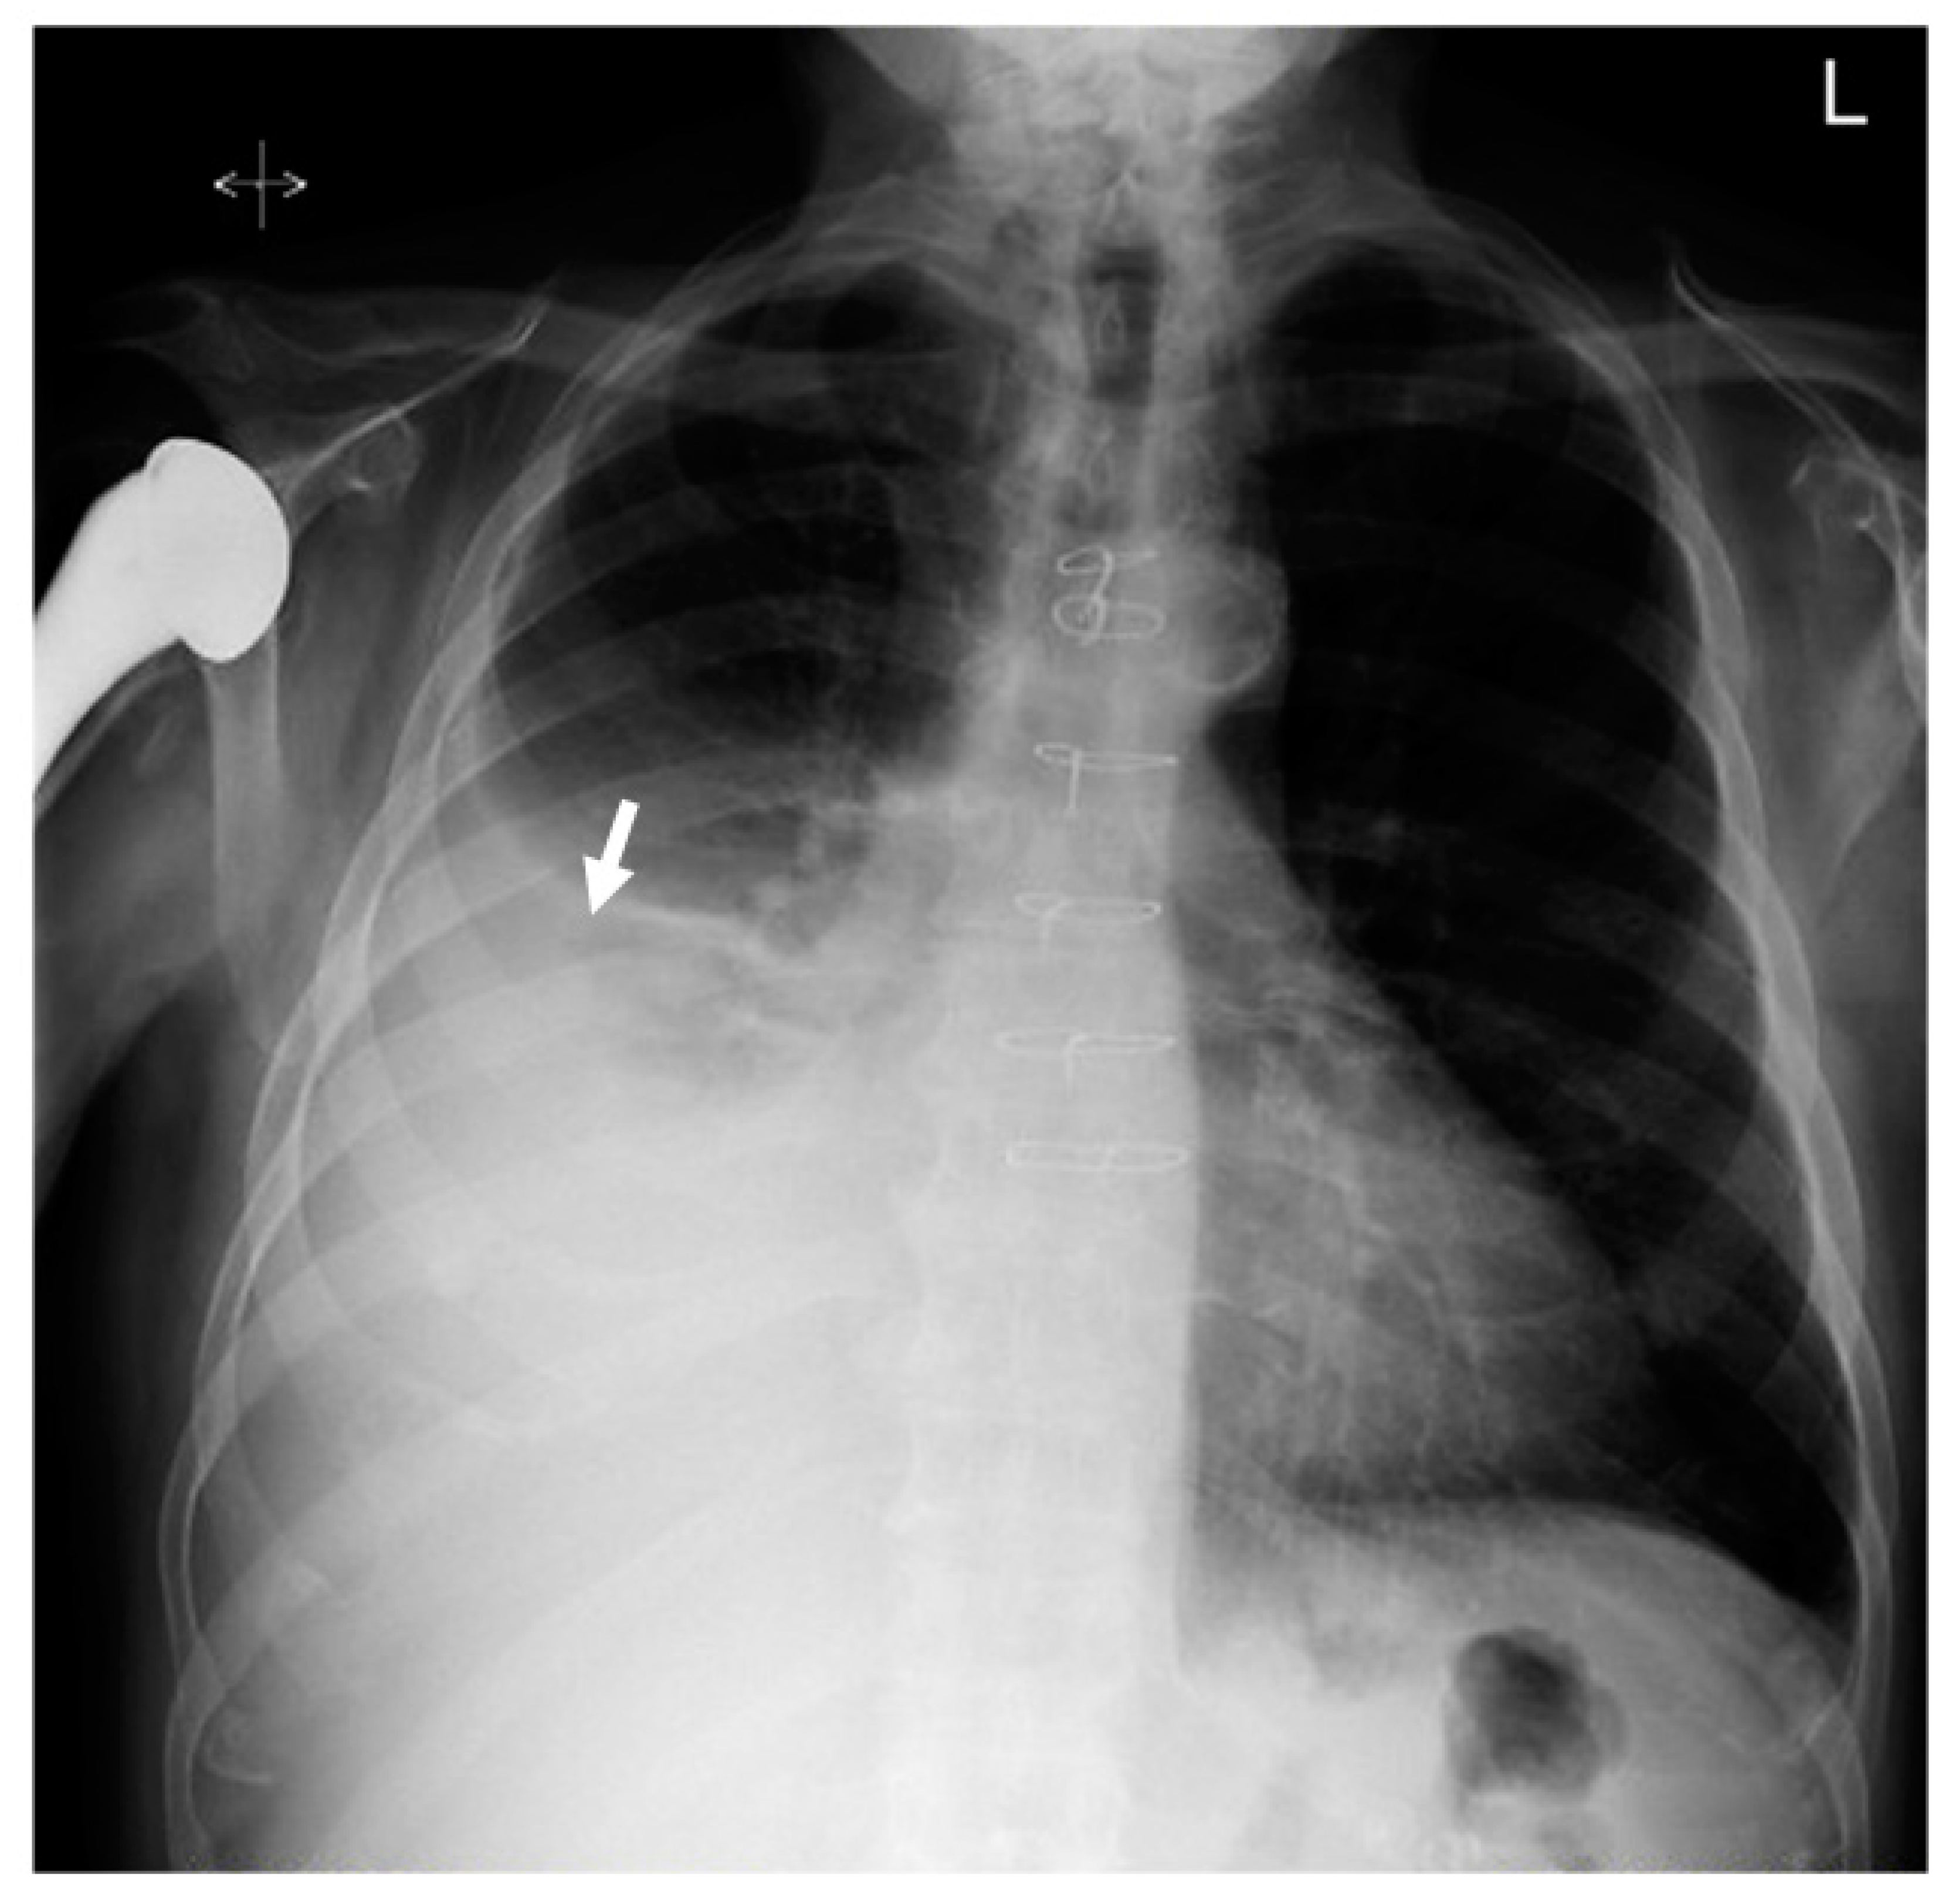

2. Case Presentation